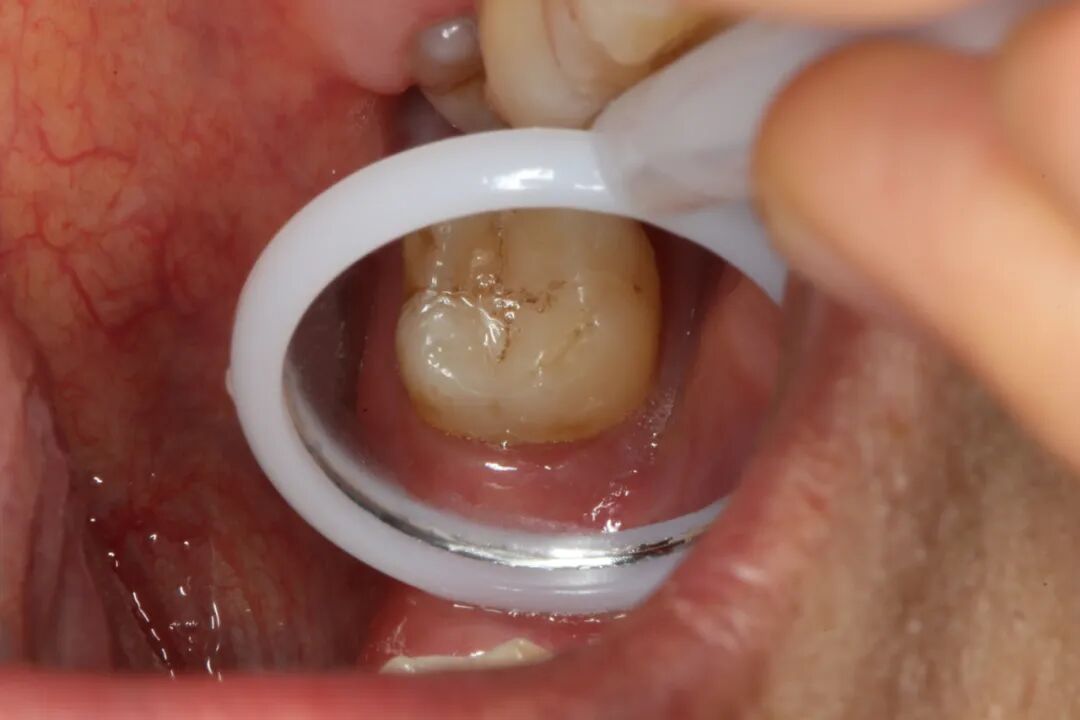

董医生结合郑先生情况,尽最大可能保住牙齿,最终给出了让患者满意的治疗方案:经过牙周刮治、根管治疗后再进行GTR手术(牙周组织再生手术),最后带上牙冠的方法,尽最大可能保留患者的天然牙。

三个月后,郑先生在董医生的再三确认后顺利戴上了牙冠。一场历时近半年的治疗,终于让他摆脱了困扰多年的牙疼,恢复了口腔健康。